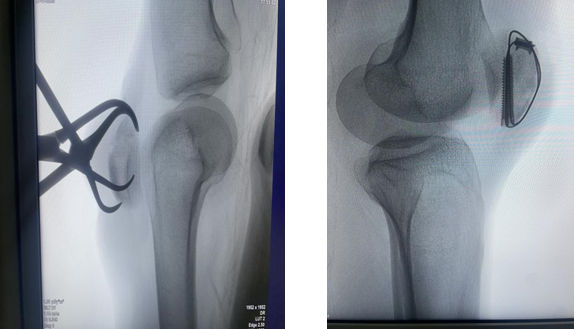

但与大家想象中“开大刀”的场景不同,西安高新医院骨科一病区杨鹏主任为她制定了一个微创手术方案。用小切口,解决大问题,杨鹏主任通过一个小切口,在X光机的“导航”下,将碎成几块的膝盖重新对拼好,然后用一套专门的内固定材料(通常是钢丝和钢钉)从内部将其牢牢固定住。这个手术的名字叫“左侧髌骨骨折闭合复位内固定术”。

简单来说,这个过程就像是,隔着皮肤拼图,医生不打开整个“盒子”,而是通过小口把里面摔碎的“拼图”(碎骨块)复位对好。再用特殊的“内置骨架”从里面把拼好的图固定住,让它能自己长牢。

手术非常成功。目前文女士的膝盖上只留下了一个小小的疤痕。术后,她已经在骨科一病区团队的指导下,开始了早期的康复锻炼。虽然完全康复还需要一段时间,但微创手术带来的小创伤和快速恢复,让她对重新正常行走充满了信心。